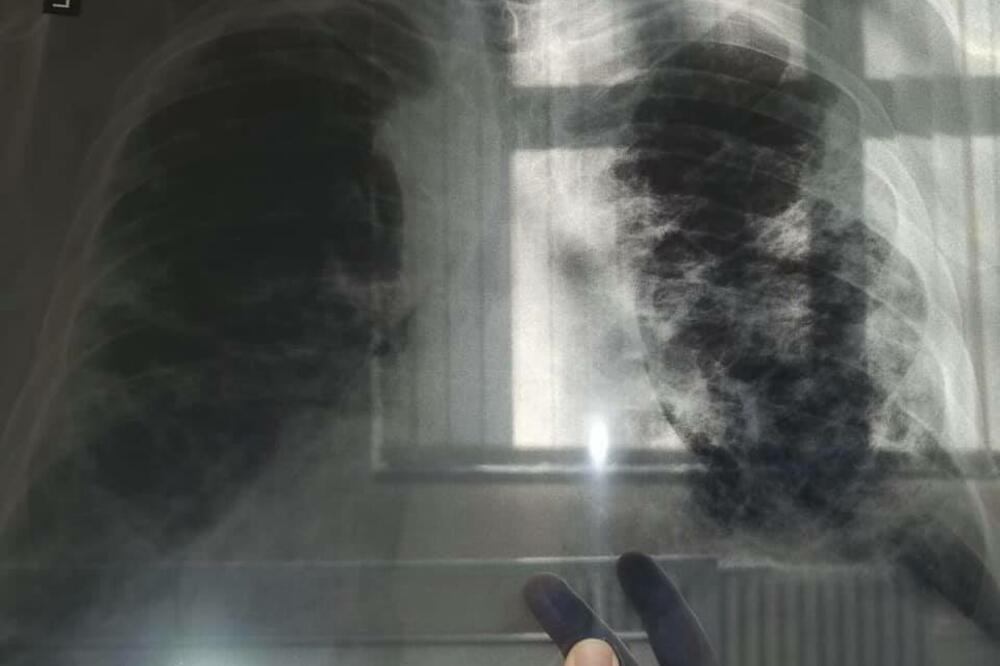

Jedna mama je upozorila sve one koji posećuju muzičke festivale da izbegavaju gas koji izaziva smeh nakon što su njenom sinu "eksplodirala" pluća

Lekari kažu da je imao sreće što je živ.

Mama Keti Meken (44) iz Elsmer Porta u Češiru rekla je: „Niko ne zna posledice. Zatim jeje dodala: „Ovo je moglo da ga ubije. "Njegova pluća imaju rupu."